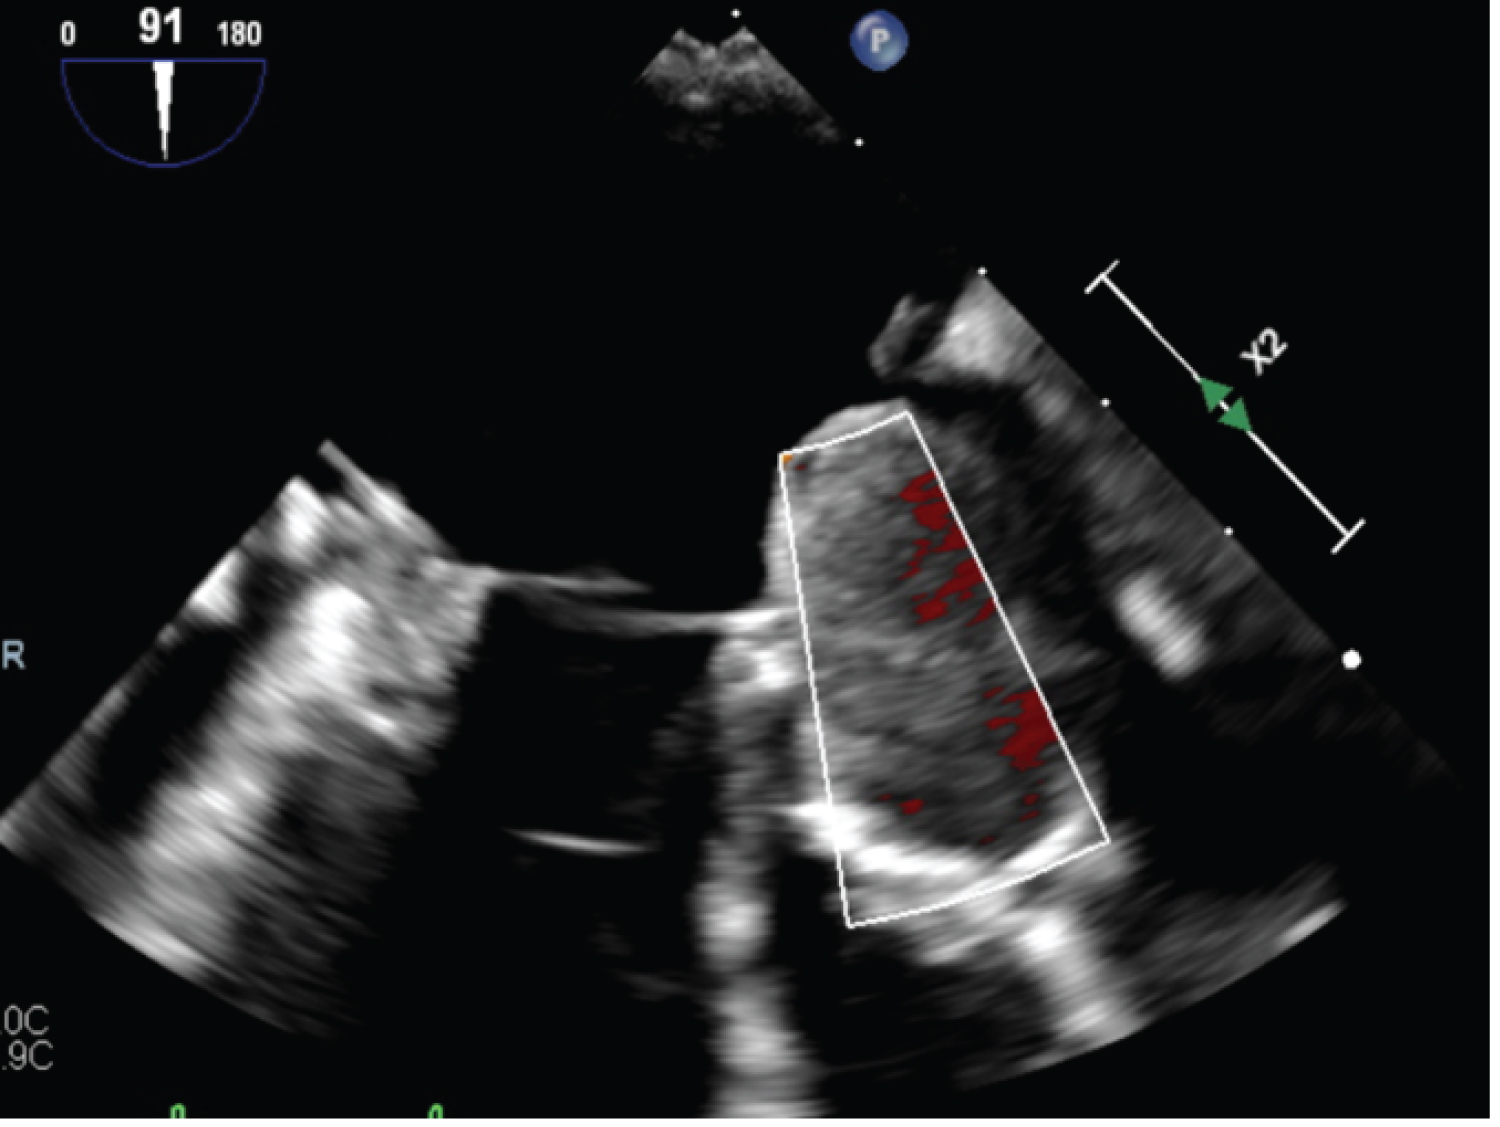

Figure 1: Large 6.2 cm × 3.5 cm left atrial mass noted on echocardiography on 11/5/22. View Figure 1

Figure 2: Large left atrial mass moving into the left ventricle across the mitral valve observed on a pre-op echocardiography. View Figure 2